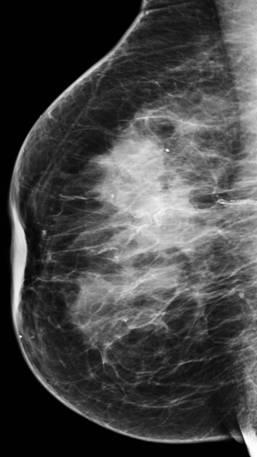

Ung thư vú

» Thông tin: Nữ giới – 76 tuổi.

» Lâm sàng: Khối tuyến vú.